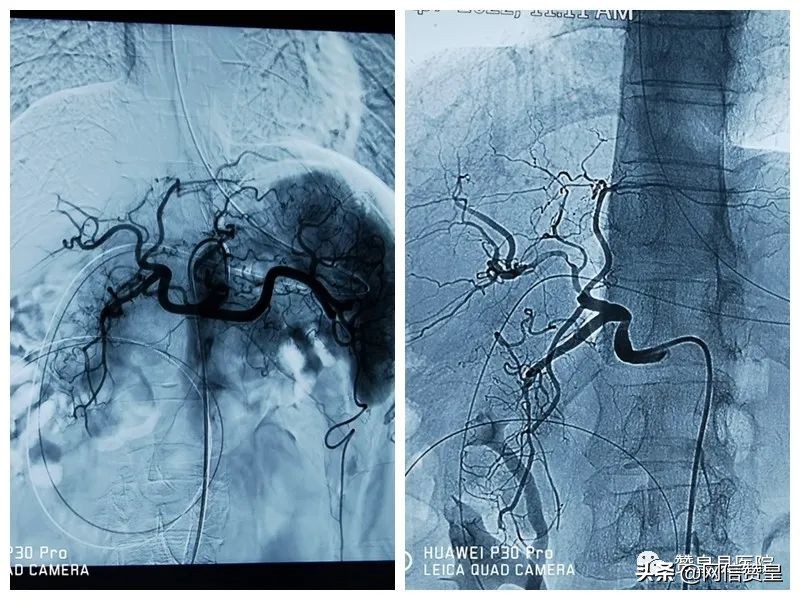

造影肿瘤显示清晰,供血丰富。